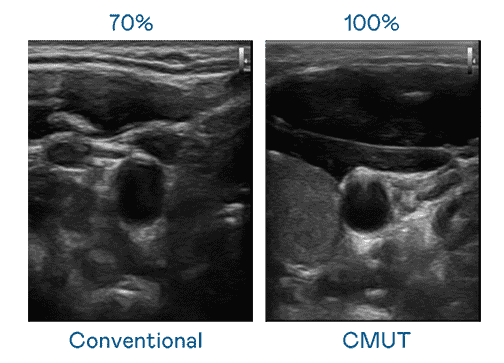

CMUT 技术是一种用电容式微机电元件来产生超音波讯号的技术。。。。与传统 PZT 压电式技术相比,,,CMUT 频宽增加 30%,,更宽频的超音波讯号让影像解析度大幅提升,,,是实现高影像品质医疗超音波扫描、、、、促进精准医疗发展的关键技术。。。

大频宽带来超清晰影像

超音波影像的解析度高低,,,首先取决于探头能发出的讯号频宽。。。。z6mg·人生就是博 CMUT 可提供高清晰的超音波讯号,,提供高频宽、、、、高灵敏度、、、影像纹理细节更高的超音波影像,,,,协助医护人员缩短影像判读时间及利用精准的医疗影像进行诊断。。。。